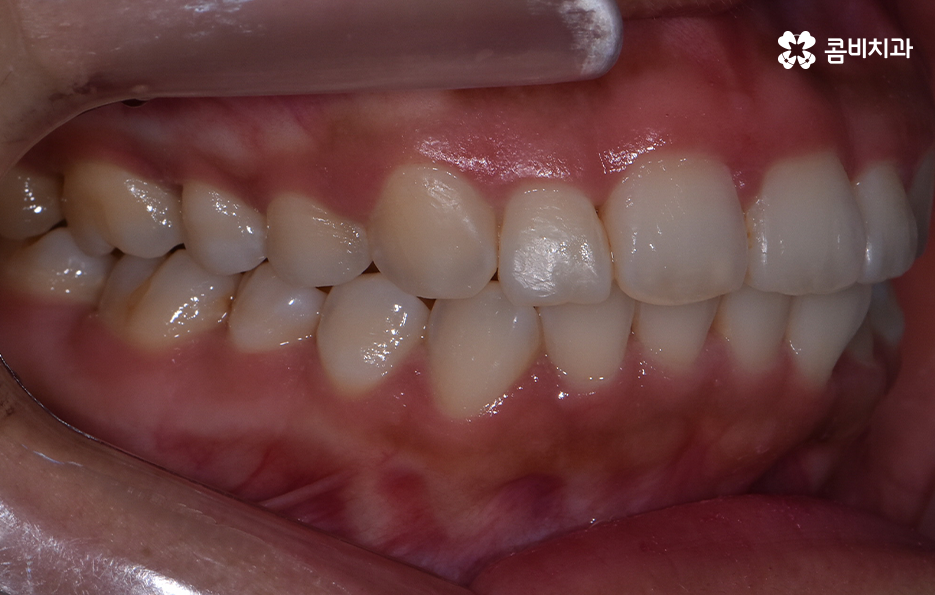

앞니 틀어짐 교정 방법 경미한 수준일 때는 부분 교정 방식은 치료 기간이나 방법 면에서 비교적 간단한 치료가 가능한데 앞니 6개 정도에만 브라켓을 부착해 미세한 틀어짐을 바로잡는 방식으로 치아가 크게 회전하지 않았거나 공간이 약간 부족한 정도라면 효과적이며 기간도 보통 3~6개월로 짧은 편으로 이 방식은 앞니 배열을 빠르게 정리하면서도 자연스러운 라인을 만들 수 있어요.

다만 부분교정 방식은 교합 문제까지 해결하기는 어렵기 때문에 교합이 안정적인 경우에 적합하기에 경미한 케이스에 적합하다고 한정 지을 수 있었어요

부분교정과 투명교정 방식은 대표적으로 앞니 틀어짐이 경미한 수준일 때 적용하기 적합한 방식이지만 교합의 개선과 얼굴형의 변화를 목표로 해야하는 경우라면 환자 분들이 앞니만 고치는 것을 원한다고 해도 전체교정이 필요한 케이스도 많기 때문에 우선적으로 정밀검진을 통해서 나에게 적합한 치료 계획을 세우는 것이 중요하겠고 치아교정의 목적에는 치료 후의 지속성, 안정성 또한 함께 고려해야 한다는 점에서 앞니 틀어짐의 원인을 개선하여 재발을 방지하는 것까지도 잘 고려하실 필요가 있었어요